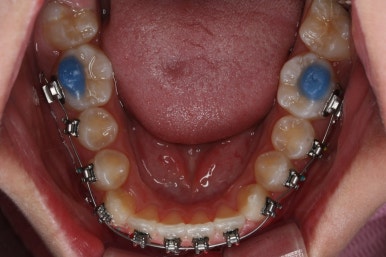

다른 앵글에서의 모습입니다.

안으로 쏙 들어가 있던 앞니가 앞으로 나오게 되면서 심미적으로 좋아지는 것을 볼 수 잇습니다.

악궁확장장치는 유지기간 이 후 다 제거가 되었고, 치아들이 매우 가지런해지는 것을 볼 수 있습니다.

이제 조금만 더 정리가 되면 장치 제거가 가능하겠네요.